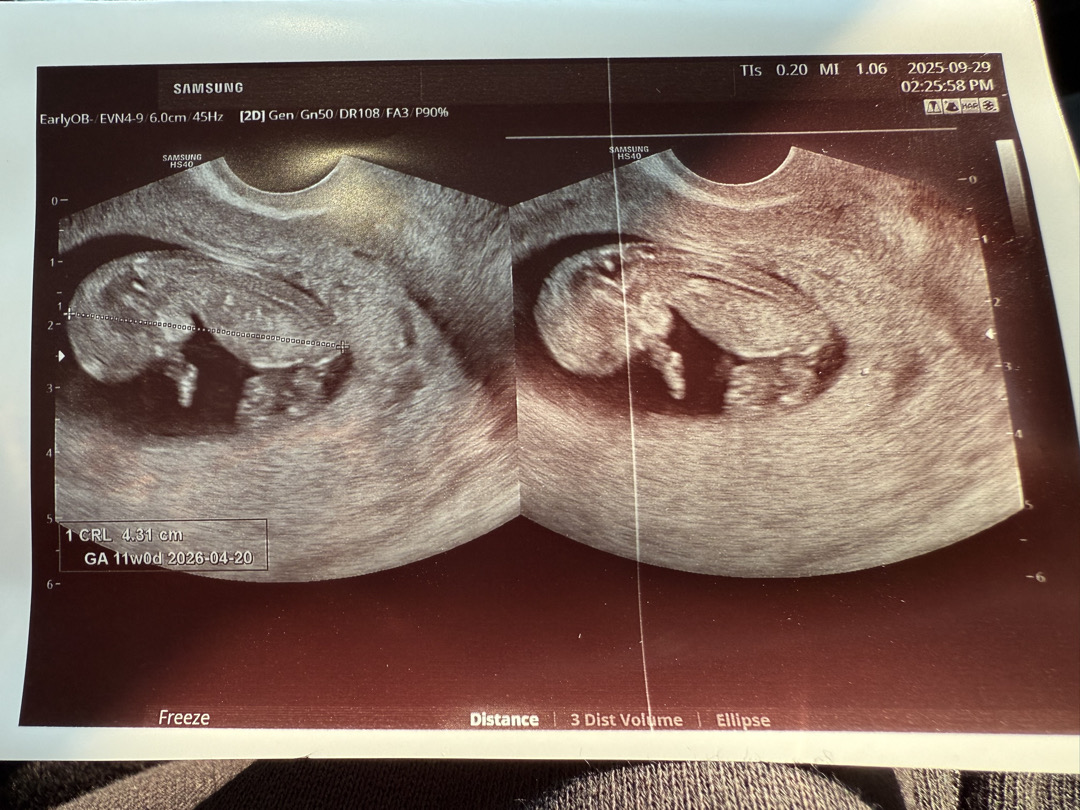

얼굴 앞에 있는 건 팔일까요???

초음파를 보고 왔는데 자세가 너무 궁금해요! 얼굴 앞에 있는건 팔인가요???